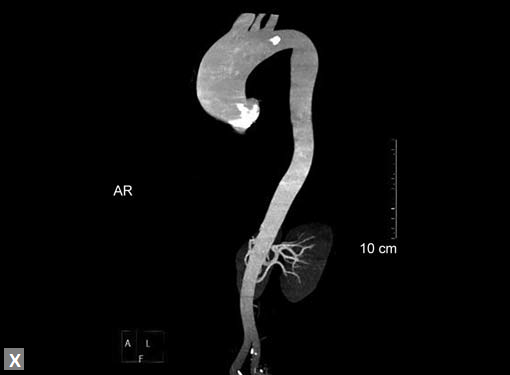

Figs 19A to Y (A to C) Scannogram (A), plain (B) and contrast study (C) show partial anomalous pulmonary venous connection; (D to F) Heterotaxy; (G) Aortic occlusion; (H and I) Aortic stents; (J) Aortic dissection with ‘Benz’ sign due to second dissection within the true lumen; (K, L and M) Aortic dissection with thrombus in pseudolumen following catheter angiogram; (N) Aortic dissection involving common carotid arteries and subclavian artery; (O, P, Q and R) Aortic dissection with right renal artery arising from true lumen and left renal artery from false lumen; (S, T, U and V) Stanford B dissection with extension Y to iliac vessels; (W to Y) Aneurysmal dilation of ascending aorta